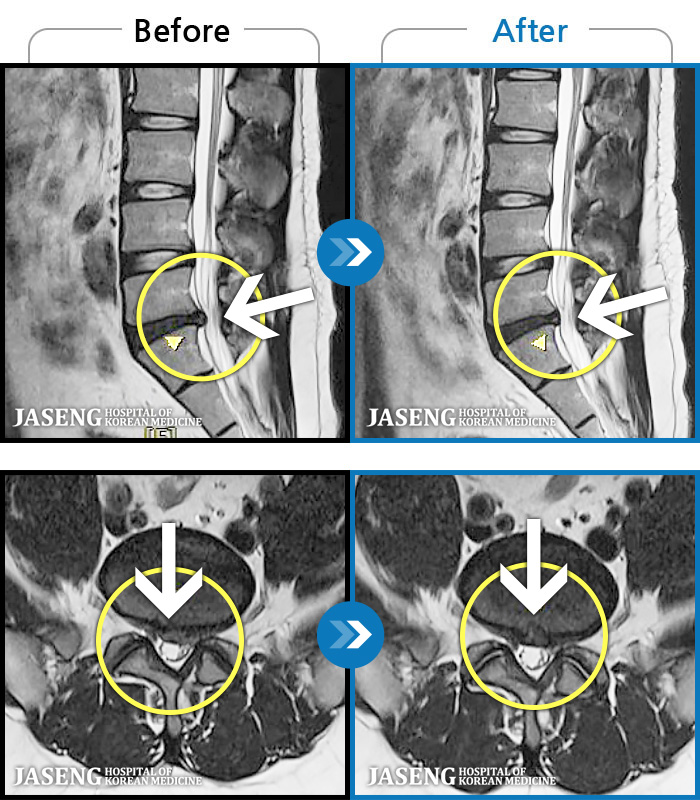

[] 03.04.01~09.11.01